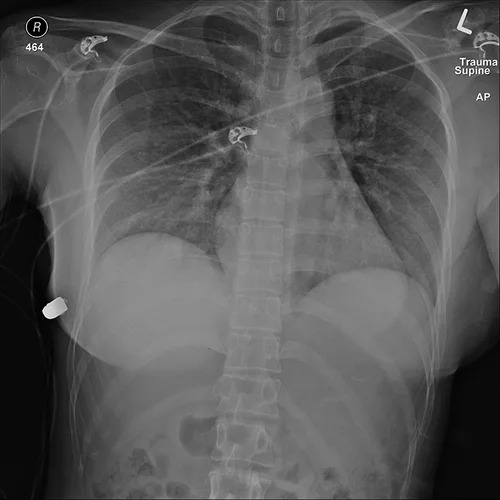

這起事件其實發生於2018年,但是以臨床案例被發表在醫學期刊上後才為人所知,當時加拿大多倫多有一名30歲女性意外被近距離槍擊,子彈打進了她的左側胸口,然而當下她卻沒有倒地,而是自己站著走路去醫院掛了急診,還能準確地說出自己的狀況,讓當地的醫護人員都受到了不小的驚嚇。

事實證明這位病患的情況真的很特殊,由於她先前有接受隆乳手術,植入了約450毫升的矽膠,所以遇害後子彈從左胸進入,在裡面彈跳之後到了右側,造成右側胸骨骨折,最後停在了右側胸下。大部分從左邊進入的槍傷患者很容易會有生命危險,因為靠近左側有心臟、肺部等重要器官。在這一起個案中,矽膠剛好擋在子彈和器官的中間,達到了保護的作用。

醫生把矽膠拿出來之後也可以清楚地看到子彈擦過的痕跡,這也太驚險了吧QQ 所以隆乳對這起個案上來說,相當於自帶安全氣囊在身上了!